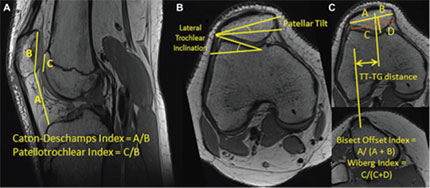

Measurements used to characterize knee anatomy and patellofemoral alignment.